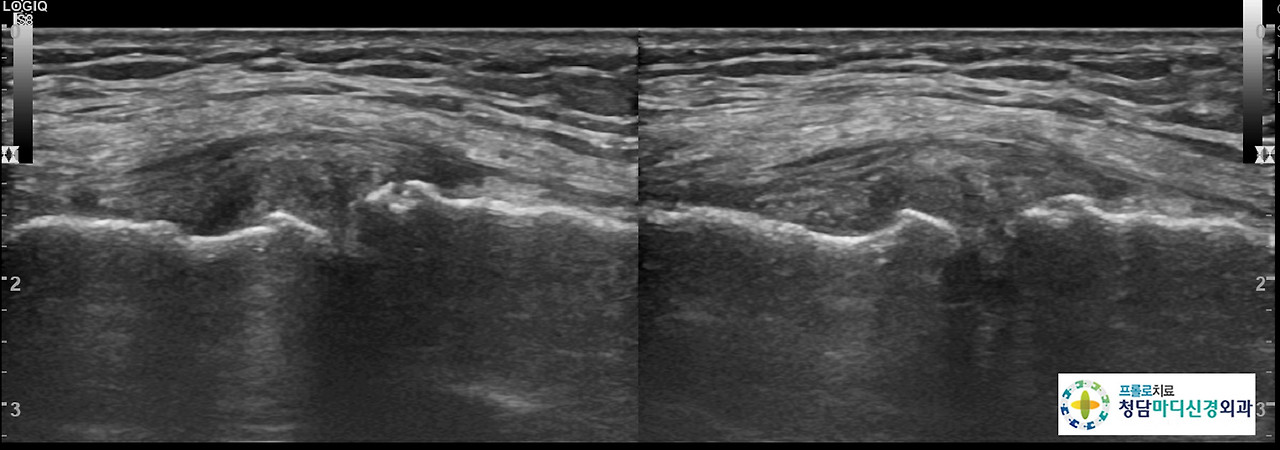

0516(3).jpg 무릎 초음파 사진

0516(4).jpg 무릎 초음파 사진

초음파 검사상에는 관절낭에 삼출액이 보이고, 대퇴골과 하퇴골의 골극을 보이면서 연골간격이 좁아진 소견을 나타냈습니다.